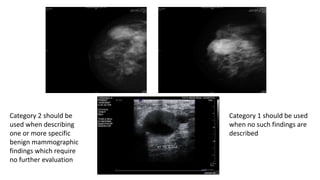

Category 1: Negative

BIRADS

Category 2: Benign finding(s):

• Like Category 1, "normal" assessment, but the interpreter chooses to

describe a benign finding

• Involuting/calcified fibroadenomas

• Multiple secretory calcifications

• Fat-containing lesions such as oil cysts, lipomas or Galactoceles

• Hamartomas

• The interpreter may also choose to describe

• Intramammary lymph nodes

• vascular calcifications

• implants or architectural distortion clearly related to prior surgery

Category 2 should be

used when describing

one or more specific

benign mammographic

findings which require

no further evaluation

Category 1 should be used

when no such findings are

described